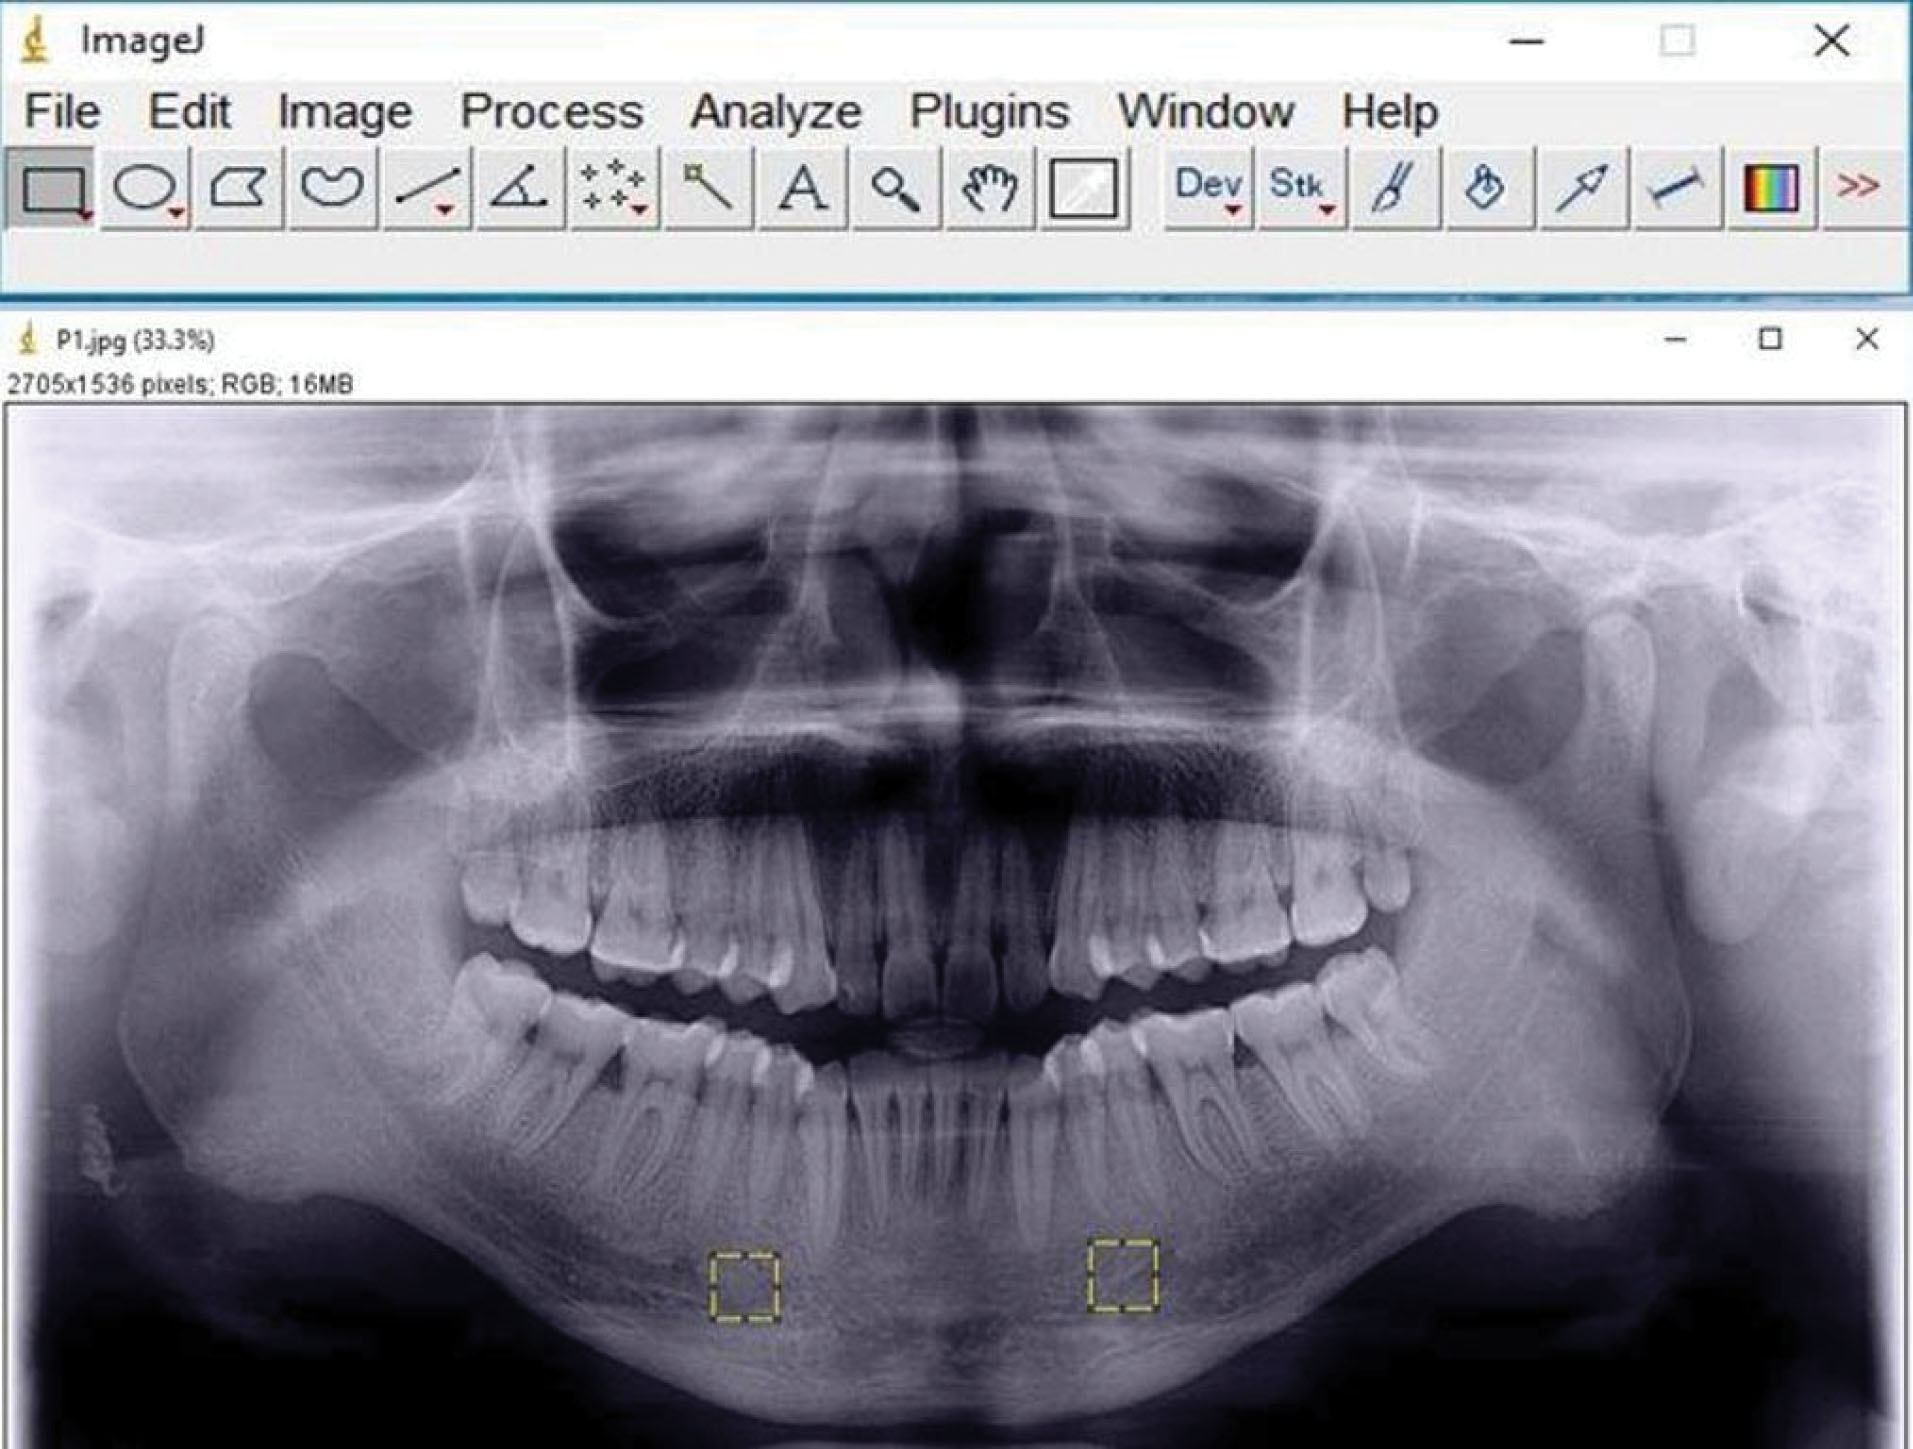

Digital panoramic radiographs of all the patients were in TIFF format, around 200 kb in size. The images were randomly shuffled and viewed on a 17-inch LED monitor with a resolution of 1024×768, 32 bits, 2 GB RAM, 1.67 GHz processor with landscape orientation under subdued lighting. The ROI, a square-shaped box of 81* 81-pixel size, was selected manually in the mandible bilaterally anterior to the mental foramen and below the root apices 8 in each radiograph to prevent the interference of hyoid bone and the effect of anatomical structures, such as mental foramen, mandibular nerve canal, lamina dura and tooth roots, on the analysis (). The selected regions of interest were processed using the method designed by White and Rudolph (). 5 The ROIs were duplicated and then blurred by a Gaussian filter with a diameter of 35 pixels. The resulting heavily blurred image was then subtracted from the original image. Bone marrow spaces and trabeculae were discriminated from each other by adding a 128-grey value to each pixel location. The image was then binarized to outline bone marrow spaces and trabeculae. The noise of the resulting image was eliminated with erosion, and the outlines of the structures were emphasized using dilation. The image was then inverted to make the trabeculae black and bone marrow spaces white. The skeletal structure indicated the bone marrow pattern, and the non-skeletal structure represented bone marrow in the skeletonized binary image. After skeletonization, the ROIs were prepared for evaluation of FD and lacunarity. 5

joddd-15-140-g001

Figure 1. Selection of the region of interest (ROI) bilaterally on a panoramic radiograph in ImageJ software.